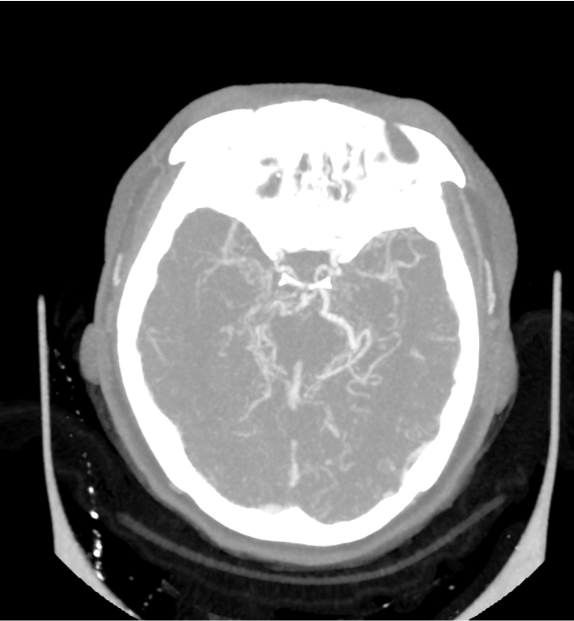

CTA